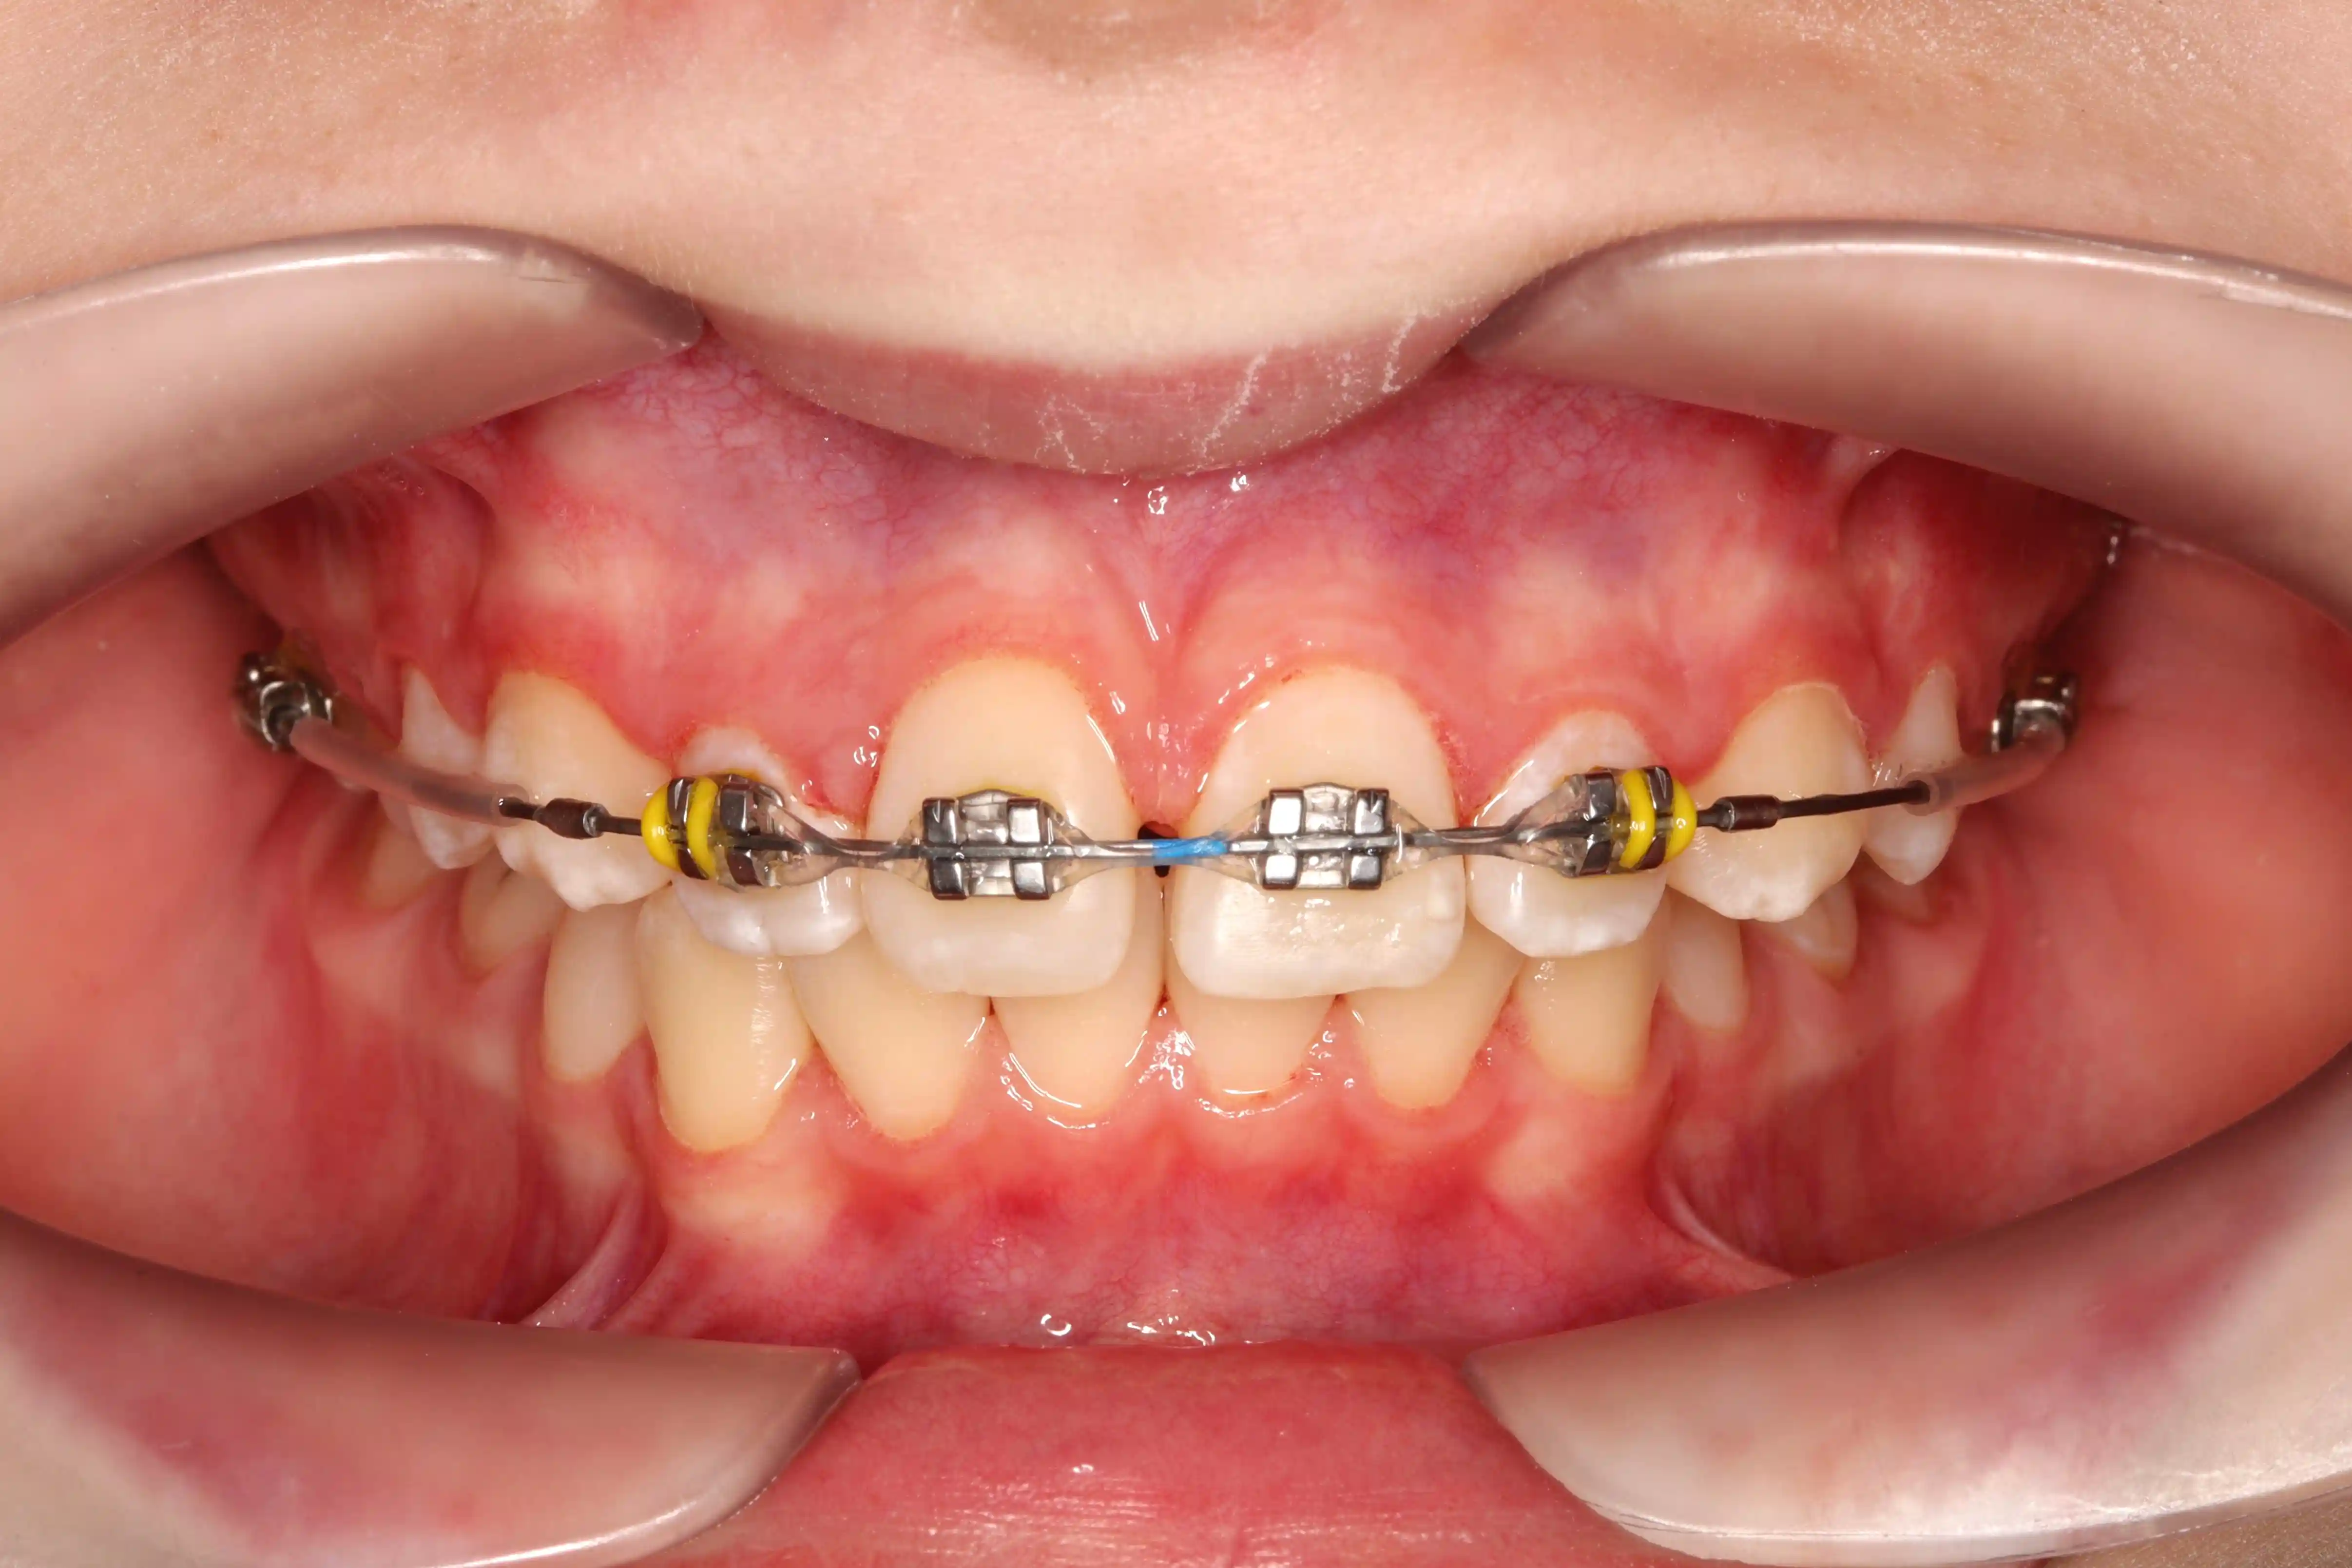

після

Результат - відновлений баланс у фронтальній ділянці, правильне положення зубів і передумови для гармонійного розвитку прикусу